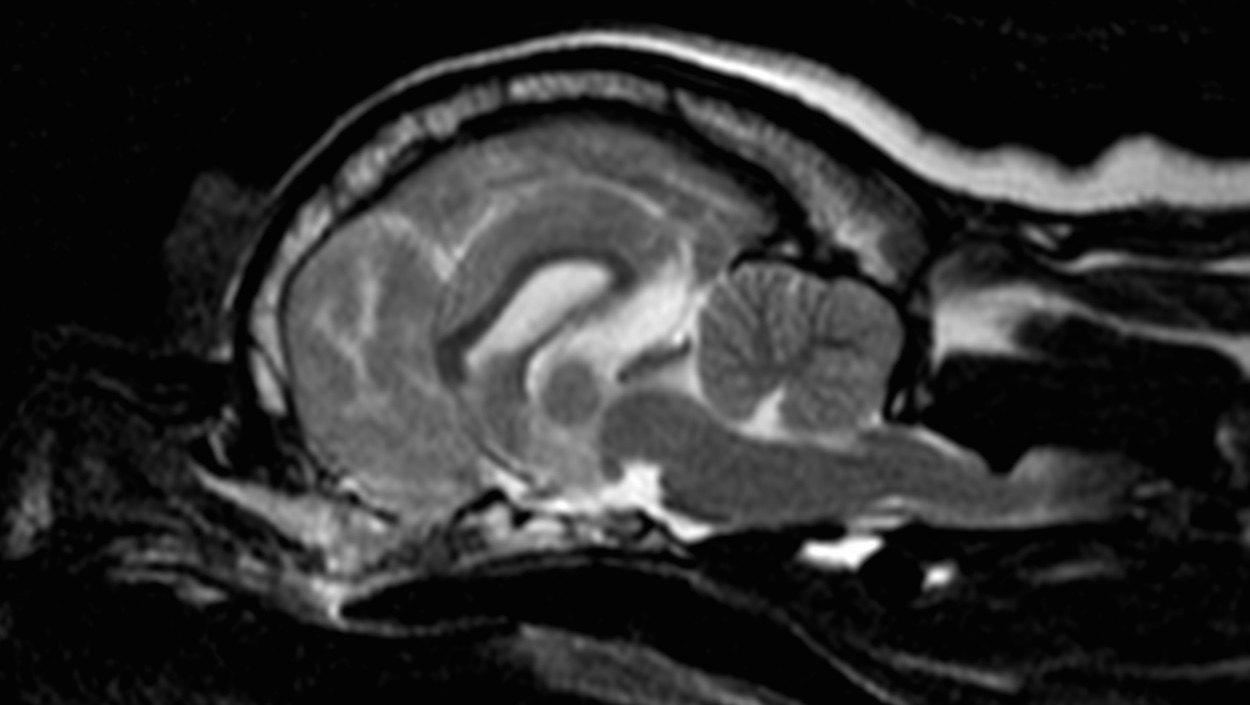

Пациент Собака породы мопс возраст 2 года Владельцы отмечают шатающуюся походку, нарушение координации, периодически испытывает болевые ощущения.

При проведении мрт выявлена дорсальная компрессия спинного мозга в сегменте между первым и вторым шейными позвонками. Это врожденная аномалия краниовертебрального перехода

Данная патология носит название впадина Дьюи